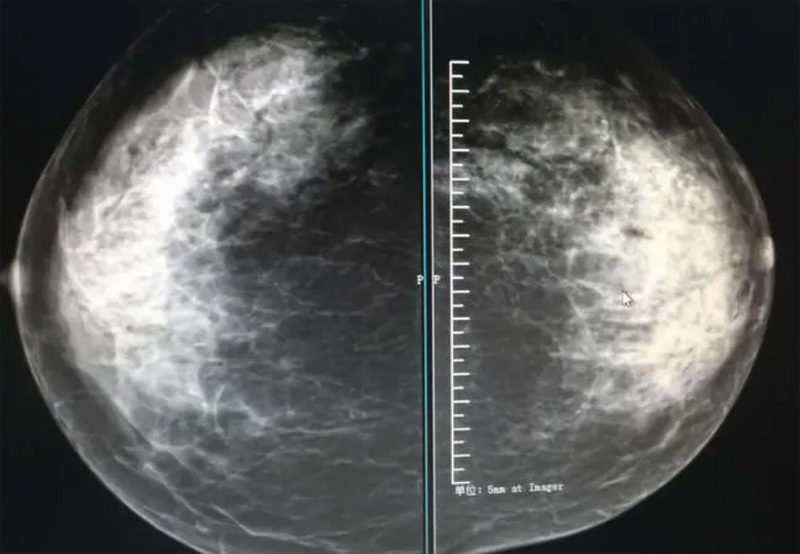

乳腺DR攝影體位有頭尾位及內(nèi)外側(cè)斜位,

乳房在片子的中央,乳頭切線位,可見(jiàn)小部分胸大肌,內(nèi)側(cè)乳腺組織應(yīng)全部包括在片中,外側(cè)乳腺組織盡可能包括在片中。一張好的MLO位圖像顯示如下:乳房被推向前上,乳腺實(shí)質(zhì)充分展開(kāi),胸大肌可見(jiàn),較松弛,下緣達(dá)到乳頭水平,乳頭在切線位,部分腹壁包括在片中,但與下部乳腺分開(kāi),絕大部分乳腺實(shí)質(zhì)顯示在片中。乳腺組織外緣可見(jiàn)乳頭的輪廓;乳腺后方的脂肪組織被很好地顯示出來(lái),乳房無(wú)皺褶。對(duì)于CC位及MLO位顯示不良或未包全的乳腺實(shí)質(zhì),可以根據(jù)病灶位置的不同選擇以下體位:外內(nèi)側(cè)位(LM)、內(nèi)外側(cè)位(ML)、內(nèi)側(cè)頭尾軸位(MCC)、外側(cè)頭尾軸位(LCC),尾葉位(CLEO)及乳溝位。在臨床實(shí)踐中,對(duì)于常規(guī)體位上發(fā)現(xiàn)的異常改變,可以進(jìn)一步采取一些特殊的攝影技術(shù),包括局部加壓攝影、放大攝影或局部加壓放大攝影技術(shù)。